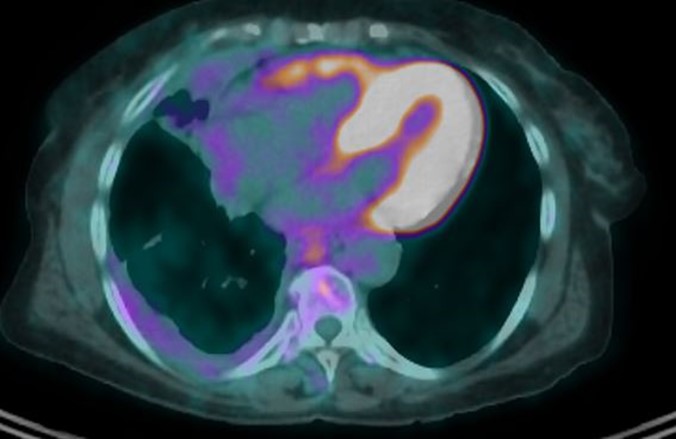

The PET-CT (Fig. 1) and pelvic MRI confirmed the thoracic and local extension without any distant, abdominal and pelvic localizations. Based on the imaging the primary diagnostic hypothesis was of a soft tissue sarcoma of the right thoracic wall with the differential diagnosis of a neglected mesothelioma.

Figure 1: Initial presentation.